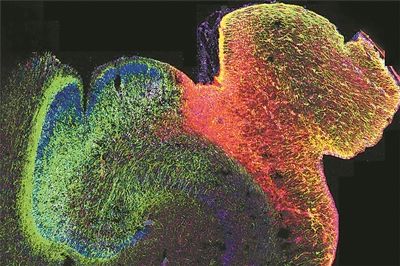

正在發(fā)育的人類海馬體的熒光圖像。圖片來(lái)源:美國(guó)加州大學(xué)舊金山分校

科技日?qǐng)?bào)北京10月9日電 (記者張佳欣)由美國(guó)加州大學(xué)洛杉磯分校牽頭的一項(xiàng)研究,揭示了人類大腦發(fā)育過(guò)程中基因調(diào)控的演變方式,并展示了染色質(zhì)的3D結(jié)構(gòu)在其中發(fā)揮的關(guān)鍵作用。研究人員繪制了海馬體和前額葉皮質(zhì)中DNA修飾的首張圖譜,這兩個(gè)大腦區(qū)域?qū)W(xué)習(xí)、記憶和情緒調(diào)節(jié)至關(guān)重要,也常與自閉癥和精神分裂癥等疾病相關(guān)。這項(xiàng)研究為早期大腦發(fā)育如何影響身心健康提供了新的見(jiàn)解。相關(guān)研究9日發(fā)表在《自然》雜志上。